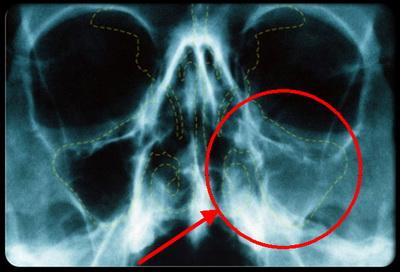

Внаслідок цього, в гайморових пазухах починається запальний процес і продукування слизу. Так як визначити гайморит по зовнішнім проявам у цій ситуації складно, то в цілях діагностики фахівці нерідко вдаються до рентгенографії.

- Рентген;

Рентген і диафаноскопия є самими простими та розповсюдженими процедурами обстеження на дитячий гайморит. З їх допомогою вдається визначити вогнище запалення і його розміри. Це обладнання є в усіх районних поліклініках, але в наші дні, для обстеження дітей старше 1 року, все ж намагаються застосовувати діагностичну техніку нового покоління, використовуючи метод комп’ютерної томографії.

З інструментальних методів діагностики найбільш поширені рентген і комп’ютерна томографія, яка показує більш точну картину захворювання.

Рентген виконується в кількох проекціях. Для цього пацієнта в різних положеннях укладають у напрямку до плівці і промені рентгена. Контрастність забезпечується за рахунок різної щільності кісток, повітря і слизової в пазухах.

Просвіт пазухи різко звужений

На знімку видно затемнення в області пазухи, ступінь якого залежить від типу виділень (серозні або гнійні). Є варіант проведення рентгенографії з контрастом. Для цього після діагностичної пункції та очищення пазух від гною вводиться спеціальна речовина.